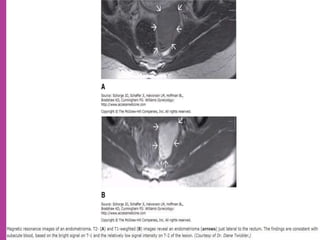

 Study ofnormal uterus and adnexa – with aim to have clear image of normal myometrium, endometrium , ovary and follicles within the ovary.  Myoma—to differentiate myoma from adenomyoma.localization of myoma—sub serous/ intra mural or sub mucous.  Adenomyosis---accurate diagnosis.  Congenital uterovaginal anomalies— bicornuate, septate,subseptate , unicornuate, didelphys ,rudimentary horn and vaginal atrasia etc

 MRI ismost sensitive for diagnosis of Adenomyosis.  MRI Is more accurate and informative in diagnosis of congenital malformation of genito-urinary tract.  Retroparitoneal lymph node > 1cm can be identified so also such small deposits on bowel / bladder liver can be identified in cases of cancers.  It is more sensitive and accurate tool to assess infiltration of myometrial/ cervical wall, adjoining organs and parametrium --thus helps in pre operative staging of genital carcinomas.  As it is safe in pregnancy –it is useful in diagnosis of obstetrical conditions as well s differentiation of tumors (benign / malignant ) complicating pregnancy.